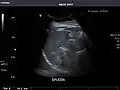

Abdominal Ultrasound (Full Exam)

STRUCTURED REPORT

(Technique: Transabdominal ultrasonography; Device: Toshiba Aplio XG)

Spleen: Normal in size.

Spleen -